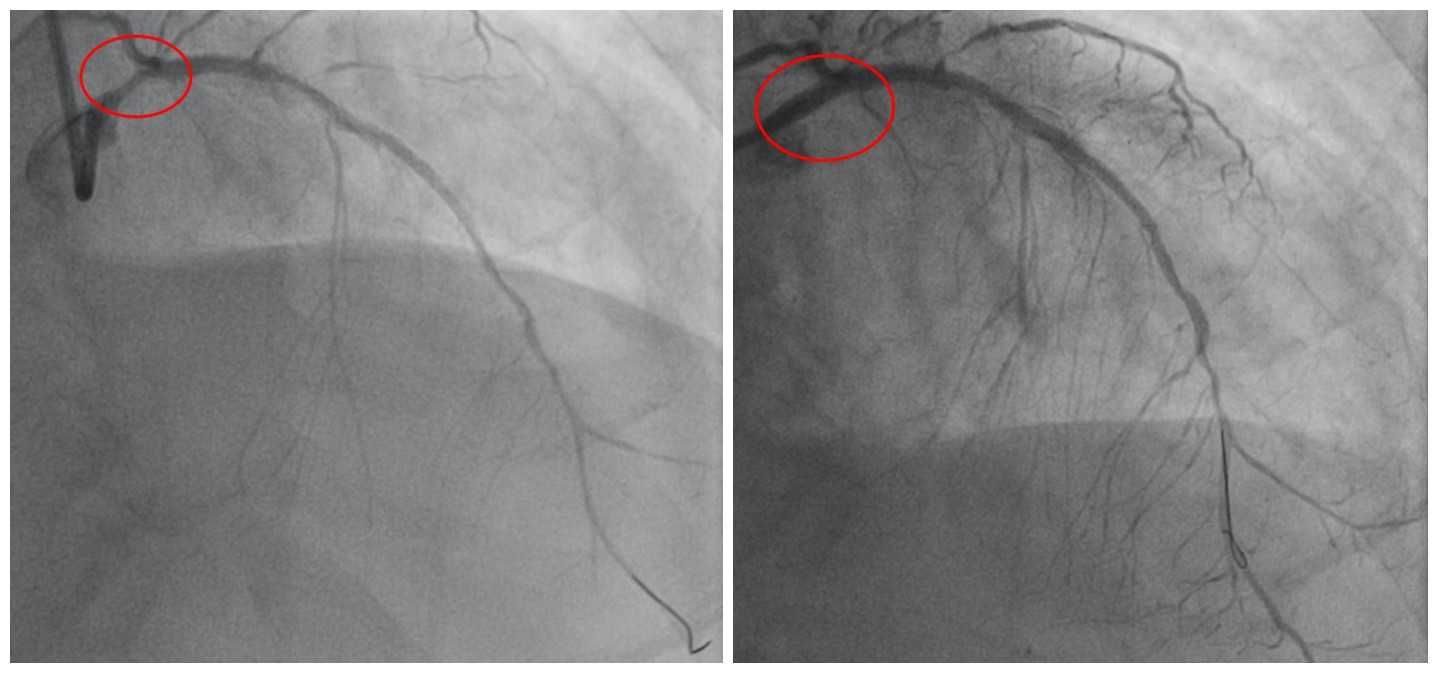

术前、术后检查结果显示,韩先生冠脉支架内在狭窄的问题被解决

韩先生到医院检查发现,心脏主要三根大血管狭窄病变严重,原来植入药物支架内也再次狭窄,

导致心脏严重缺血。近一个月来,韩先生辗转多家医院,均被建议做冠脉搭桥术,但考虑到冠脉搭桥手术恢复、住院周期长、风险大,他十分犹豫,但病情逐渐加重,韩先生不得不考虑接受手术,遂到捷克论坛 心血管内科,准备控制心衰后做冠脉搭桥术。

认为左主干狭窄90%,原支架内再狭窄是导致患者心衰根本原因,因而解决支架内再狭窄是当务之急,可以在原支架内狭窄部位再次植入药物支架,避免搭桥手术,与患者和家属充分沟通后,制定了微创介入治疗方案。

潘宏伟主任分析患者心脏仅靠“一丝”血流维持血供,且球囊扩张狭窄处时心脏无法再次耐受缺血,随时可发生心脏骤停等危险,在团队紧密配合下,最终在数分钟内迅速在左主干狭窄部位植入药物支架、原支架内行球囊扩张术,成功解除了再狭窄问题,恢复心脏血流挽救生命。